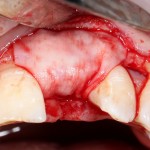

Другой вариант. Имплантируем, но существующего объема костной ткани недостаточно для получения адекватного эстетического и функционального результата:

Поэтому мы используем мембрану Geistlich BioGide и всё ту же аутокостную стружку: